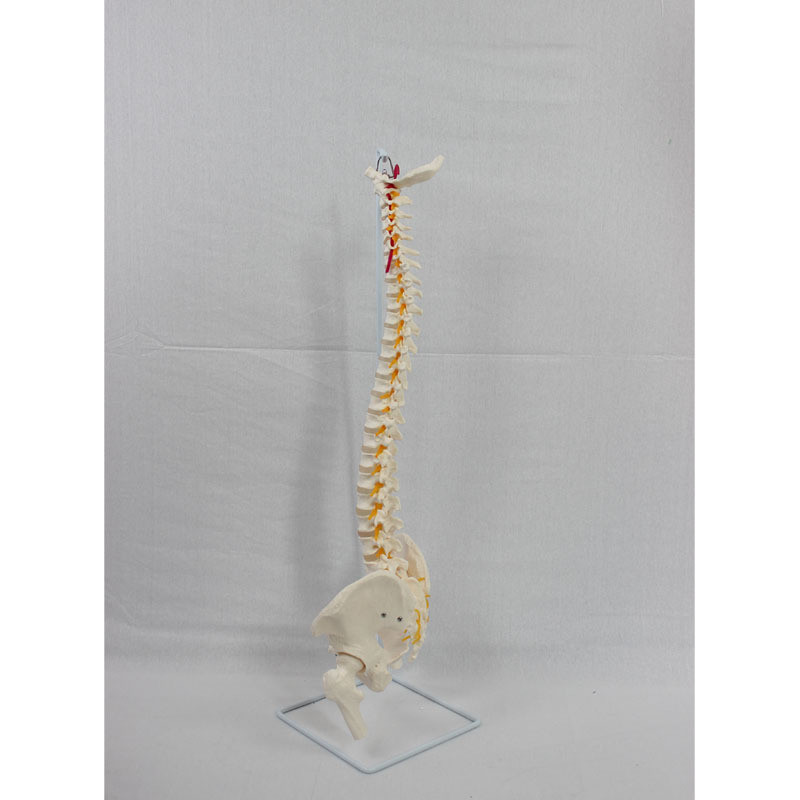

自然大脊椎枕骨和新骨盆带股骨模型 人体脊椎模型